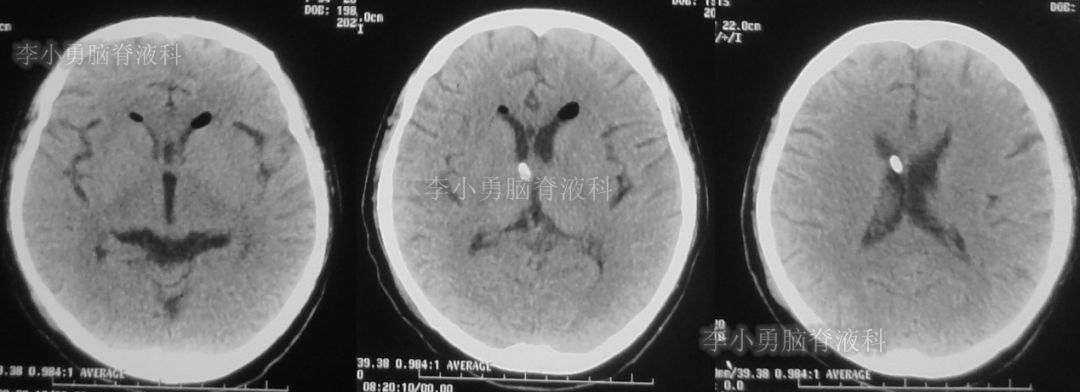

此次分流泵调压后1个月,即2018年12月11日,患者第3次出现头痛,而且头痛逐渐加重并昏迷,急到当地的第1家医院行头颅CT(图-7)见脑室从缩小又变成扩大状态。

图-7:2018年12月11日头颅CT

第3次调压后18天,即2018年12月29日,患者恢复好,在当地第1家医院复查头CT(图-8)见脑室明显缩小。

图-8:2018年12月29日头颅CT